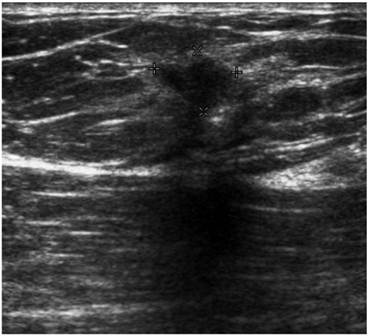

Screening MRI of both breasts performed 15 months later demonstrated interval development of a 1.1 cm enhancing ill-defined mass at the 1 o'clock axis of the left breast (Figure 1). A corresponding solid hypoechoic mass with angulated margins was seen on targeted left breast ultrasound (Figure 2). Mammography demonstrated heterogeneously dense breast tissue with post surgical changes bilaterally. No dominant mass or suspicious clustered microcalcifications were identified in either breast (Figure 3). Ultrasound guided core biopsy yielded moderately differentiated invasive ductal carcinoma.

Figure 2

Targeted ultrasound of the left breast demonstrating a solid hypoechoic lesion at the 1 o'clock axis which corresponded to the enhancing lesion on the MRI.